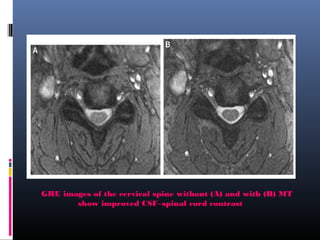

GRE images of the cervical spine without (A) and with (B) MT

show improved CSF–spinal cord contrast

• 115.

GRE images ofthe cervical spine without (A) and with (B) MT show improved CSF–spinal cord contrast